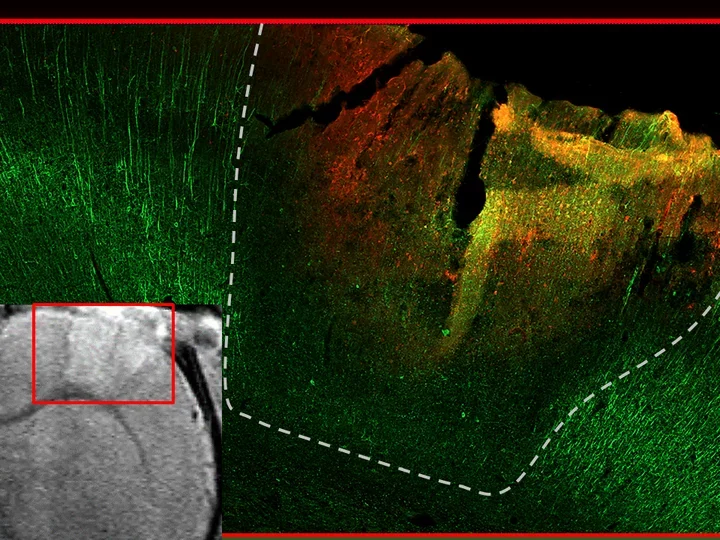

Neuronal landscape from healthy to injured rat brains: Top micrograph show healthy rat cortex with bright neuronal stain (Neurofilament light, NFL, green). Middle/bottom depict 1 month postinjury cortical contusion with neurodegeneration (NFL loss) and glial scarring (GFAP, red). Mediolateral traces of NFL loss for each injured rat contrast with normal averages (dotted green line with green variance band). Comparisons span both cortical gray matter (center) and corpus callosum white matter (right).

Internal validity is documented by aligning in vivo structural MRI hyperintensity (courtesy Neil Harris, UCLA) with postmortem acute loss of neuronal fiber signal  (Neurofilament light, green) around bleeds in the contused core visualized on immunofluorescence stained histological sections that are co-registered with one another in the same rat six hours after injury.